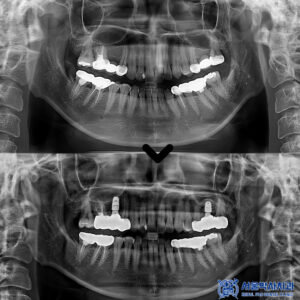

우선, 심한 치주염이 진행된 앞니 두 개를

발치한 뒤 바로 임플란트를

식립하는 방식으로

치료 계획을 세웠습니다.

발치 즉시 임플란트를 식립하면

치료 기간을 단축할 수 있고,

잇몸과 뼈가 자연스럽게 아물면서

임플란트가 더 안정적으로

자리 잡는다는 장점이 있습니다.

다만, 환자분의 경우

치조골이 많이 부족한 상태여서

임플란트 식립과 동시에 뼈 이식도

함께 진행하기로 했습니다.

치료 후 2개월이 지나고 임플란트가 잇몸과

뼈에 잘 자리 잡았는지 확인한 뒤

최종 보철물을 세팅하는

단계로 넘어갔는데요.